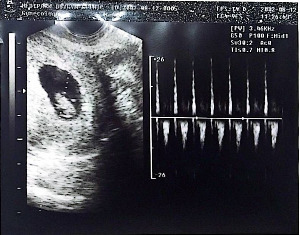

초음파로 너의 모습을 봤단다. 아직 사람의 모양이 아니지만 너의 존재를 확인할 수 있어서 엄마는 너무너무 기뻤단다. 특히 힘차게 뛰는 너의 심장소리를 듣게 되어 좋았어. 건강하게 무럭무럭 자라렴.

너의 첫 초음파 사진을 찍었단다. 엄마랑 아빠는 개구리 같다고 너를 놀렸어. 하지만 너는 심장을 움직이며 우리에게 인사를 했단다.

KakaoTalk_20250804_083950274.jpg 아이의 모습이 찍힌 첫 초음파 사진